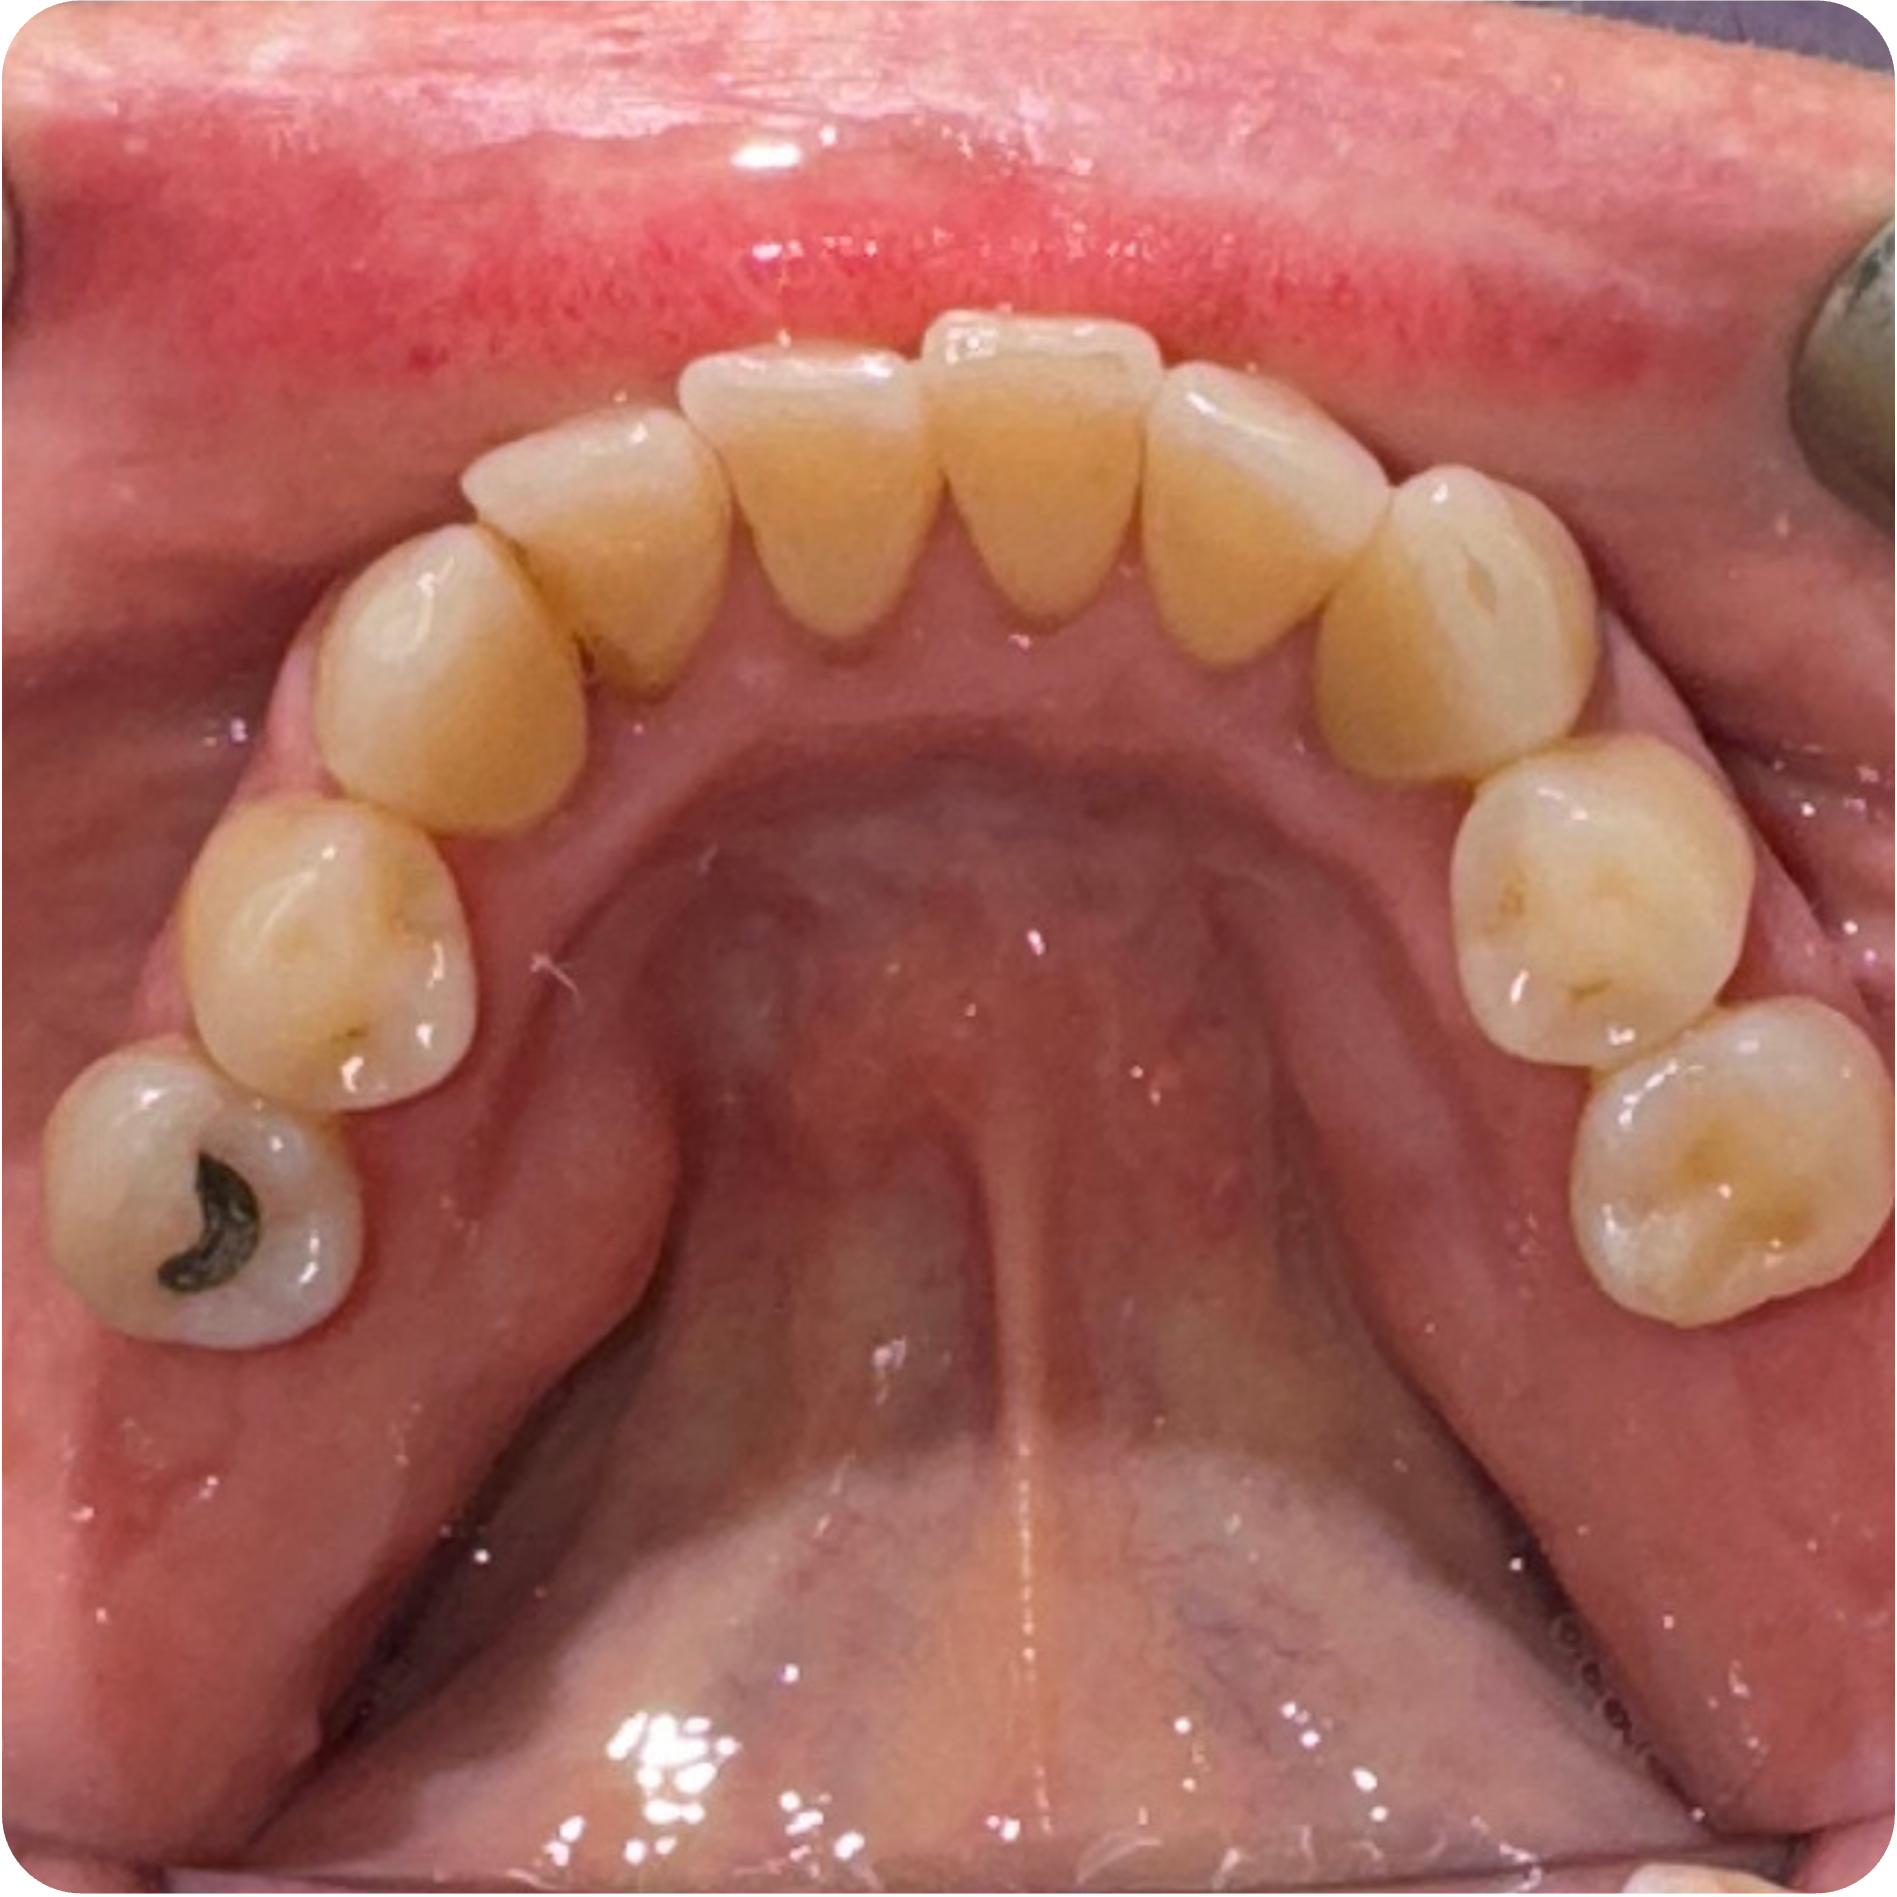

Visual Case Progression

All clinical images are shown at a consistent size for easy comparison.

Before & After (Groton Wellness Perio Protocol)